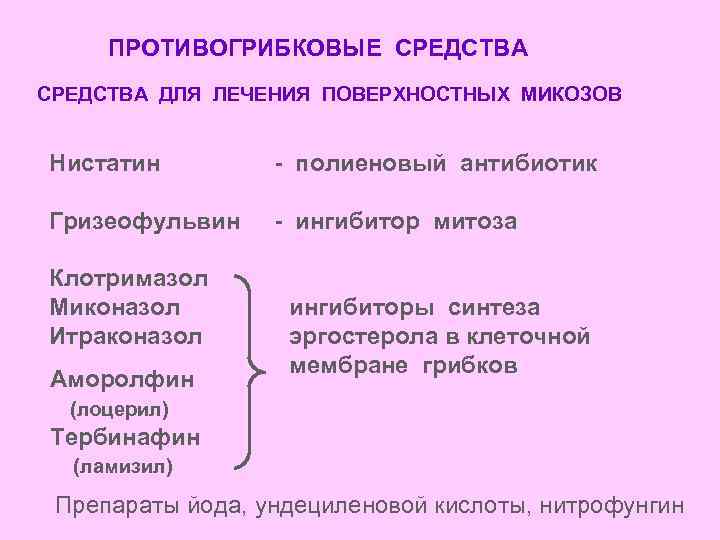

ПРОТИВОГРИБКОВЫЕ СРЕДСТВА ДЛЯ ЛЕЧЕНИЯ ПОВЕРХНОСТНЫХ МИКОЗОВ Нистатин - полиеновый антибиотик Гризеофульвин - ингибитор митоза Клотримазол Миконазол Итраконазол Аморолфин ингибиторы синтеза эргостерола в клеточной мембране грибков (лоцерил) Тербинафин (ламизил) Препараты йода, ундециленовой кислоты, нитрофунгин